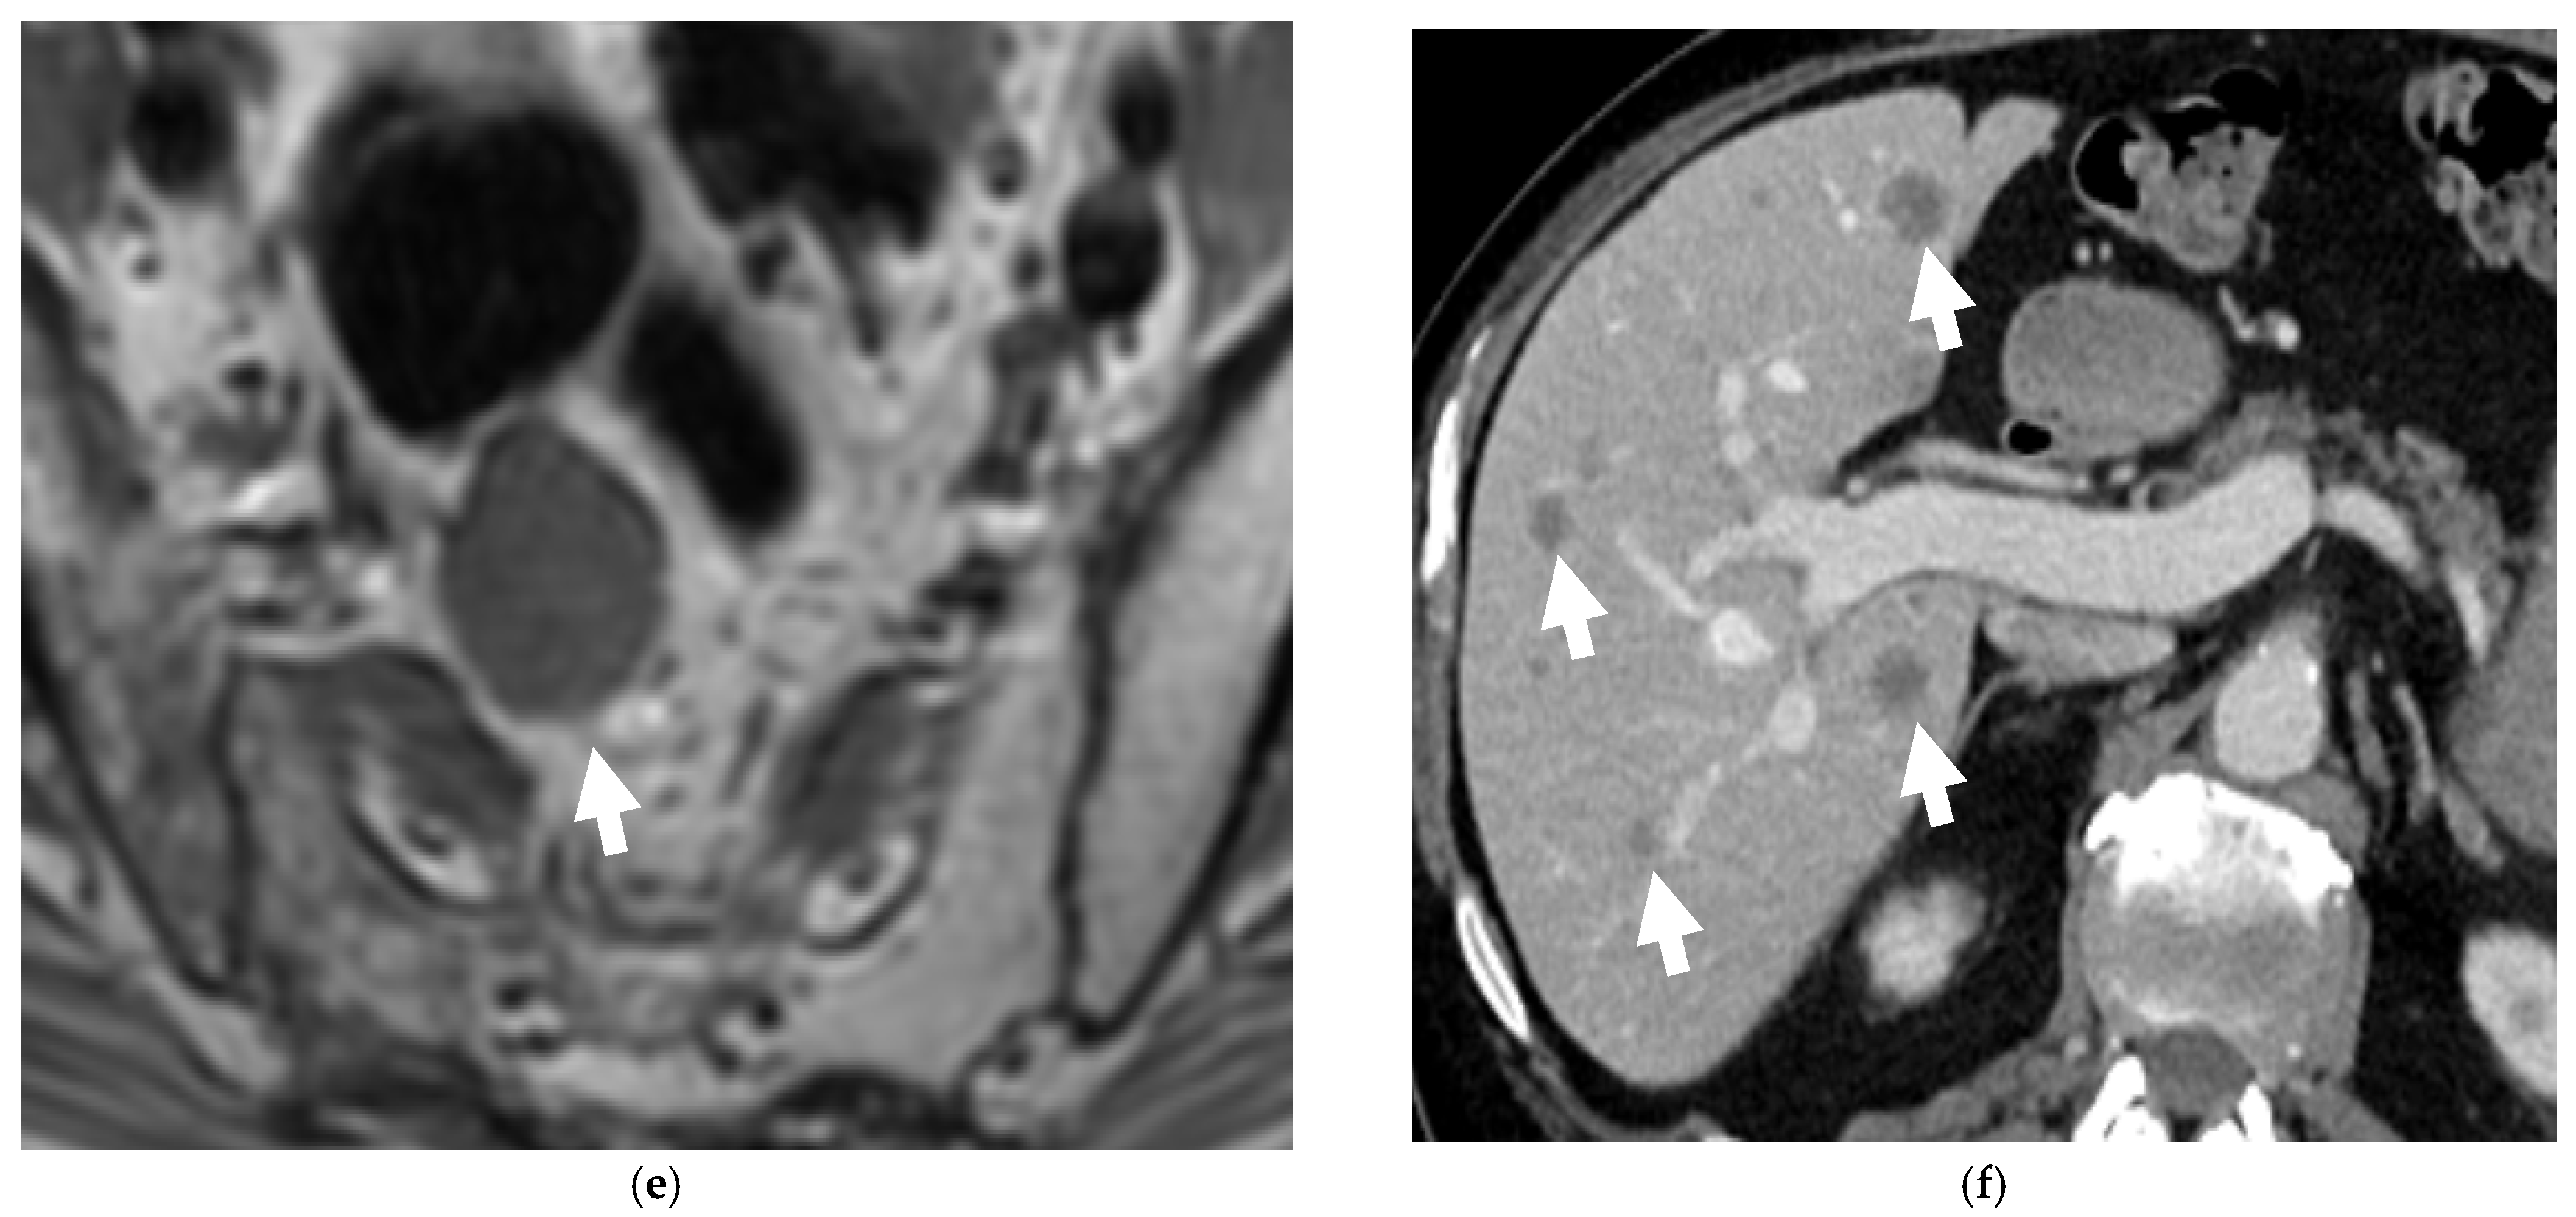

An elderly patient with metastatic neuroendocrine prostate cancer. Coronal maximum intensity projection (MIP) PET image (a) and axial color fused image of 68Ga DOTANOC PET-CT (b) show intensely hypermetabolic prostatic mass (long arrow) consistent with neuroendocrine prostate cancer and hypermetabolic widespread bony metastases (short arrows). Post-treatment DOTANOC PET-CT following 4 cycles of PRRT therapy shows marked positive treatment response. There was near complete metabolic response in the bony metastases, as seen on the coronal MIP PET image (c) with minimal residual metabolic activity corresponding to some sclerotic bony metastases on axial color fused PET-CT image (d). There is also interval decrease in the extent and degree of hypermetabolic activity in the prostatic malignancy with residual activity suspicious for residual viable malignancy. Image courtesy: Divya Yadav, M.D.

2.3.2. 68 Gallium Labelled Somatostatin Analogs (68Ga-DOTATATE or 68Ga-DOTANOC)

From an imaging point of view, the most commonly employed imaging modalities for prostate biopsies and cancer detections are multiparametric ultrasound (US) and magnetic resonance imaging (MRI). Computed tomography (CT) is reserved for staging purposes. Thus far, conventional imaging methods cannot directly differentiate between NEPCs and prostatic adenocarcinoma; however, the presence of nodal and visceral metastases and rapid progression may suggest NEPC, which often requires histopathologic confirmation [74,75]. Various PET tracers are now available for the imaging of prostate cancer and neuroendocrine differentiation. A recent clinical case series demonstrated excellent detection rates for the metastases (95%), specifically the visceral and nodal metastases in NEPCs by using FDG-PET [51,52]. The positron-emitting somatostatin analogs, which bind to somatostatin receptors (SSRTs) with high affinity, 68 Ga-DOTATATE or 68 Ga DOTANOC are also suitable and found to be as highly accurate as the PET/CT radiotracers, for the display of somatostatin-expressing NETs [43,44]. Usmani et al. reported a case that showed the significance of somatostatin receptor scintigraphy for the detection of neuroendocrine differentiation of metastatic prostate cancer [76]. In another study of 12 patients with metastatic NEPC previously treated with ADT, 50% of the patients showed a moderate or high tracer uptake in the metastases on the 68 Ga-DOTATATE-PET/CT. Further research with higher numbers of cases is required to assess the performance of 68 Ga-Somatostatin analog-PET/CT as a new diagnostic tool for prostatic neuroendocrine neoplasms [55].

Similar to most other neuroendocrine tumors, such as small-cell lung cancer, NEPC tends to be sensitive to chemotherapy and radiotherapy. Currently, treatment of NEPCs consists mainly of prostatectomy with adjuvant platinum-based regimens. Cisplatin/carboplatin combinations with either docetaxel or etoposide, have relatively high response rates. The addition of doxorubicin to regimens has not demonstrated advantages and is associated with increased side effects [79,80,81]. In a recent study, Apostolidis et al. concluded that NEPCs can be treated similar to NETs of the gastrointestinal tract, with somatostatin analogs, everolimus, and peptide receptor radionuclide therapy (PRRT) (Figure 5) [82]. Adjuvant radiotherapy is also very important, particularly when positive surgical margins are identified [80]. Targeted therapy is an exciting new therapy for NEPCs, as early evidence suggests improved clinical outcomes. Alisertib, an agent that can inhibit the interaction between N-myc and its stabilizing factor Aurora-A, has recently entered into a phase II clinical trial. It inhibits N-myc signaling, which is a driver of NEPC progression and thus, suppresses tumor growth [83,84].